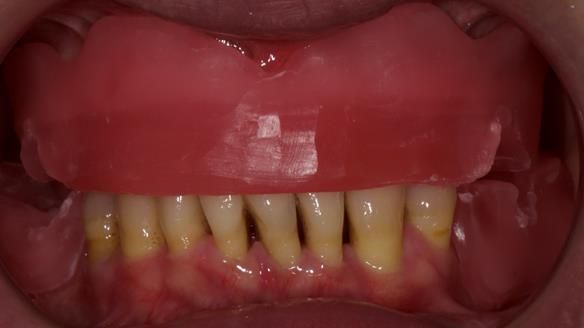

She had previously suffered from generalised periodontitis – stage IV, grade C, currently stable, with reduced attachment across the upper arch.

By the time she came to me, her periodontal condition was stable — but the aesthetics in the upper jaw were very poor.

Dr Syed Abad — my colleague and a Specialist in Periodontics — had successfully stabilised her gum health.

We provided her with an immediate upper denture (Mk 1), followed by a definitive metal-based upper denture (Mk 2). A lower removable partial denture was discussed, to be made only if needed once the upper treatment was complete. However, at review, this wasn’t necessary — Adnana had excellent neuromuscular control and function, even with a shortened dental arch (SDA).